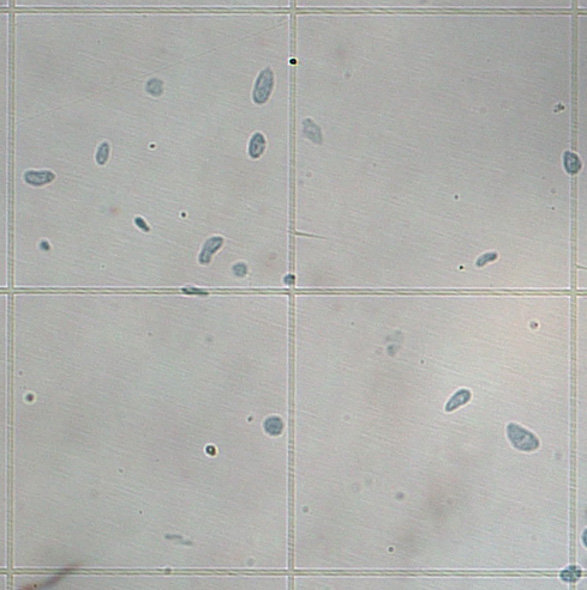

次世代シーケンス